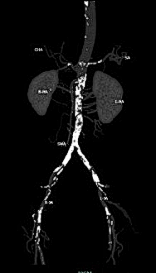

术前CTA:腹主及双侧髂动脉多处钙化病变伴管腔狭窄。

★ 造影评估

经腹主动脉造影如术中所见双侧髂动脉中-重度狭窄。

★ 术后造影

左右髂外动脉狭窄明显好转

★ 术后CTA

显示钙化病变重塑,双侧髂动脉管腔较前明显改善